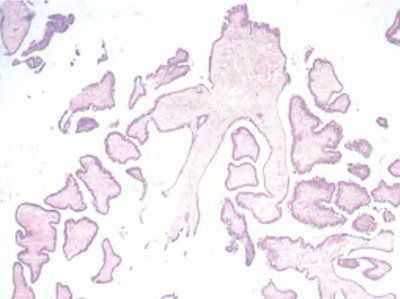

Фото 3. Легкая степень дольковой неоплазии. Общее строение дольки сохранено, однако количество долек значительно увеличено, отмечается выработка секрета, эпителий мелкий мономорфный. Гематоксилин-эозин, х 100